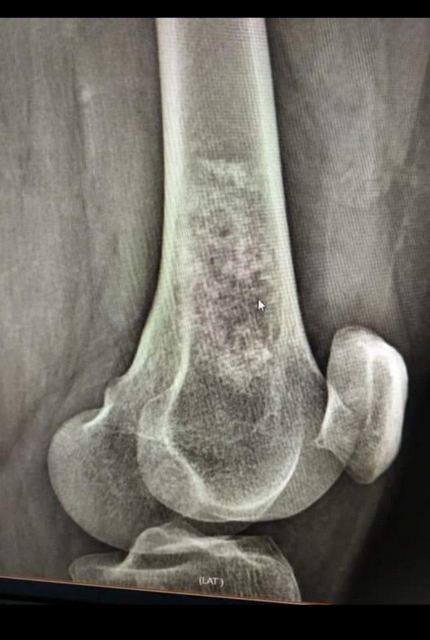

Уже більше, ніж пів року, розповідає Олеся Кондратюк, вона страждає на біль у суглобі та кульгавість. Спершу вона не звертала на це уваги. А в січні жінка впала на коліно та дуже забилася. Тоді ж біль посилився, й оперативно довелося зробити рентген. Як наслідок, побачили пухлину. Уже після біопсії в Києві та Харкові виявилося, що вона злоякісна. Жінку направили в Інститут патології хребта та суглобів ім. професора М. Г. Ситенка НАМН «України» (м. Харків), де вона нині й перебуває.

Нижче – фотопідтвердження діагнозу співробітниці «Нової якості», рентген- і КТ-знімки пухлини.